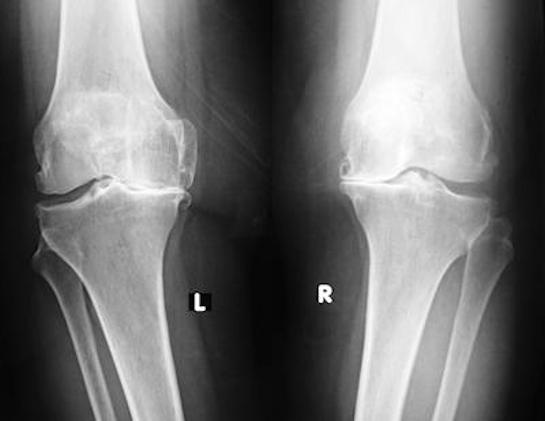

Kireçlenme nedir

Halk arasında kireçlenme olarak bilinen hastalık ya da tıbbi adı ile “artroz” veya “osteoartrit” eklemlerde meydana gelen aşınma ve yıpranma sonucu ortaya çıkar. Kemiklerimizi birbirine bağlayan eklemlerimizde, karşılıklı kemik yüzeyleri üzerini kaplayan ve ağrısız ve kaygan hareketi sağlayan eklem kıkırdağı bulunur. Yıllar içinde bu parlak ve düzgün yüzeyli doku aşınır, eskir ve yer yer dökülerek altındaki kemik ortaya çıkar. Yaygın inanışın aksine, artrozda eklemlerde kireç birikmesi söz konusu değildir.